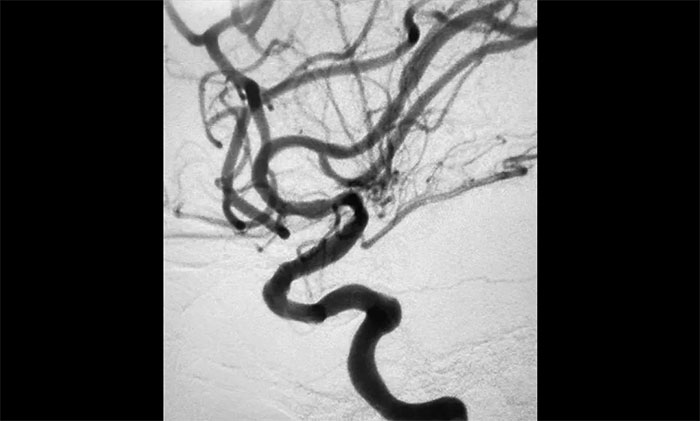

▲术后DSA影像:左侧颈内动脉血流恢复

随后,微导丝超选至左侧大脑中动脉M1段远端,并以多枚球囊扩张残余重度狭窄处,造影提示狭窄较前明显改善,远端血流改善明显。最后顺利放入支架,造影提示支架贴壁良好,支架内血流通畅,远端血流良好,手术顺利完成。